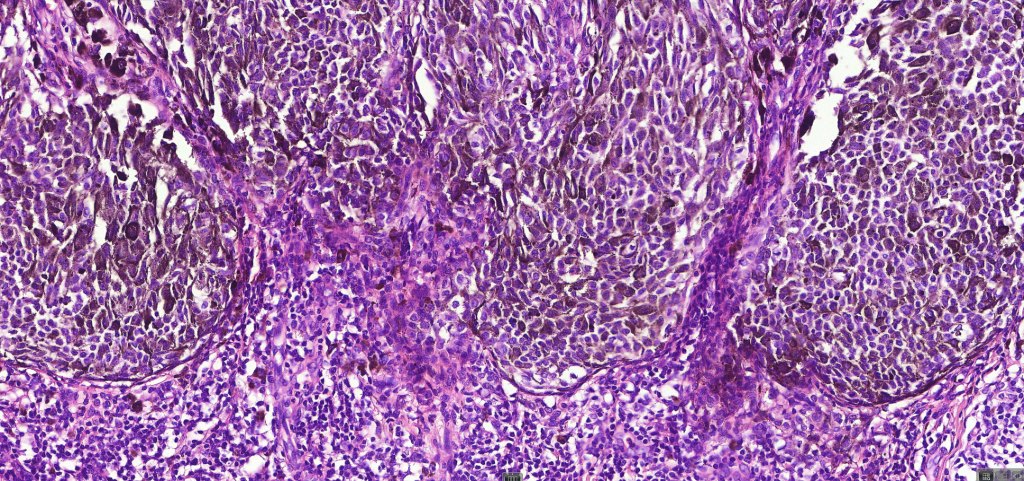

•Maturation in compound variants

•Spindle cells with small nucleoli

•Mild pleomorphism

•80 % kinase fusions (NTRK3-58%), HMB45 diminishes with depth in compound lesions